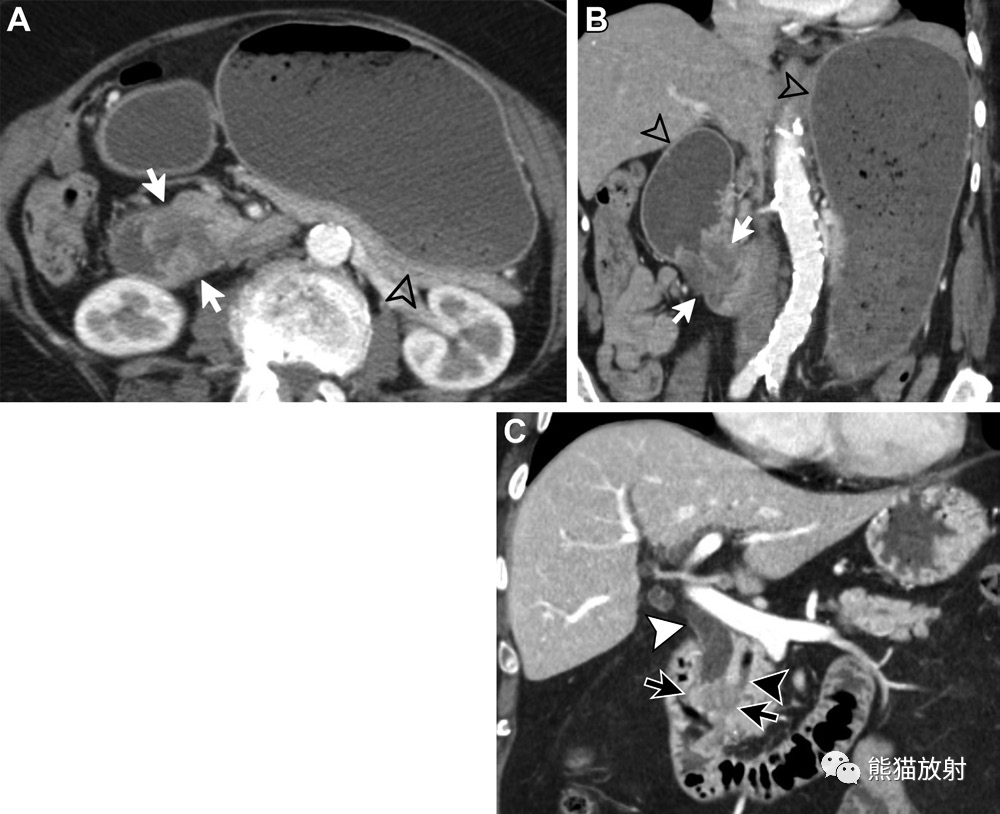

62岁男性,胰腺导管腺癌(pancreatic ductal adenocarcinoma,PDAC)。(A)轴位对比增强CT图像显示弱强化的PDG肿块(白箭)直接侵犯十二指肠内侧壁(黑箭头)和 IVC(白箭头)。注意CBD管径正常(黑箭)。(B)冠状增强CT图像显示PDG(白箭)有一个与十二指肠不可分离的弱强化肿块,形态不规则(箭头),与直接侵犯有关。注意转移性的门静脉周围肿大淋巴结(*),CBD和胰管的管径正常(黑箭),符合胰头内侧的PDAC,未累及胰胆管。